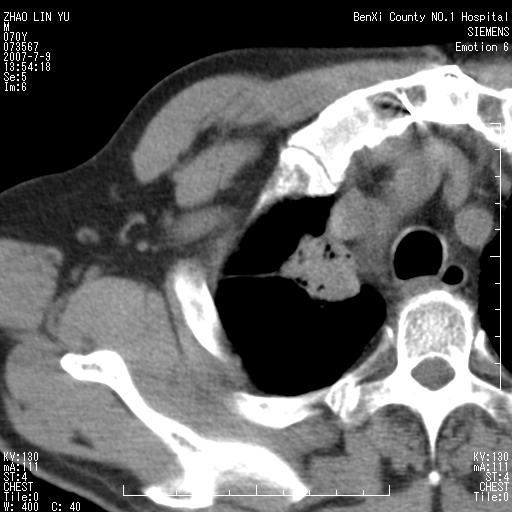

以下是引用王靖旗在2007-7-10 17:12:00的发言:[br] 男、70、咳嗽两个月,半年前换瓣手术,胸片未见异常,于昨天行x片发现右肺上野大片影,行ct扫描,这里是减薄图像,余肺正常。明天晚上会有增强扫描片,到时我会上传。[br][br] 冠状位请大家细看,应该是有意义的,[br][br] 请大家先看平扫发表意见。[br][br]

以下是引用zhangzhongshou在2007-7-10 21:43:00的发言:[br]右肺上叶周围型肺癌,以孤立型细支气管肺泡癌可能性大。